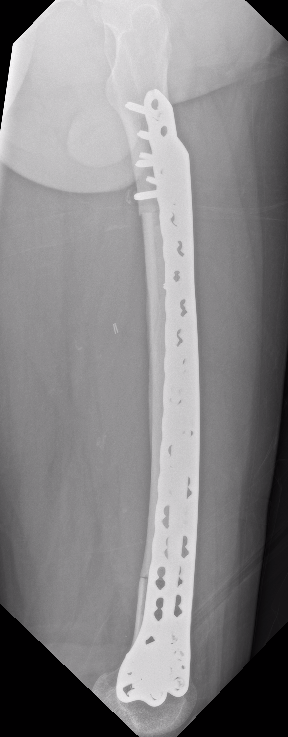

Management

Algorithm

1. Neoadjuvent chemotherapy

2. Restage

3. Surgical resection

4. Chemotherapy

5. Radiotherapy - if margins inadequate

Wide Resection - limb salvage / amputation

2 cm margin of normal tissue if able